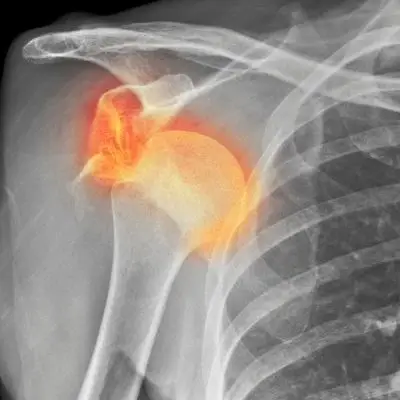

Fractures of the upper arm (humerus bone) will often occur at the proximal end of the bone, affecting the shoulder. More information about these injuries can be found in our Shoulder Injuries page.